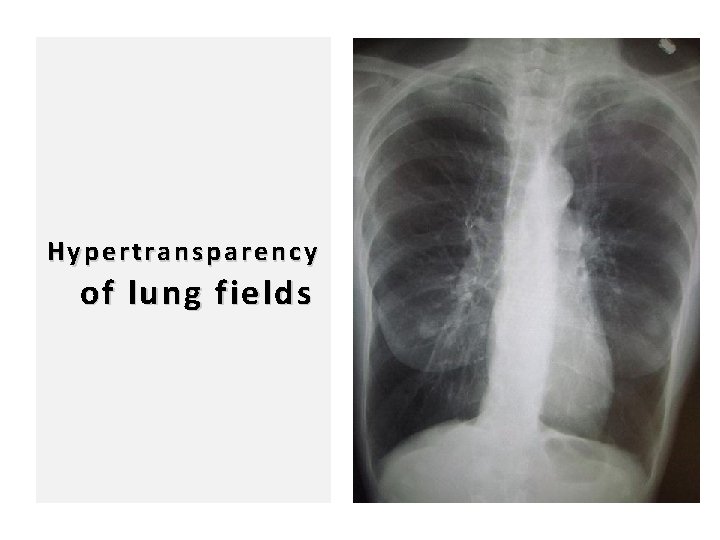

96 Hypertransparency of lung fields